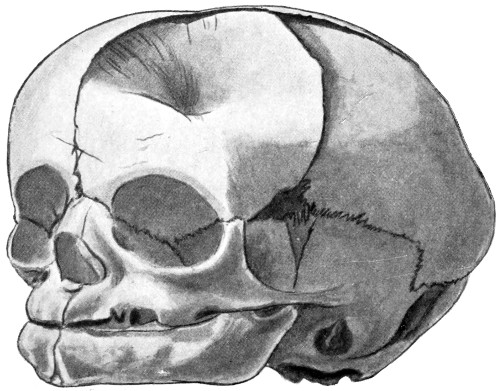

23. A depressed birth-fracture 45

24 A and B. A case of depressed birth-fracture, before and after operation 47